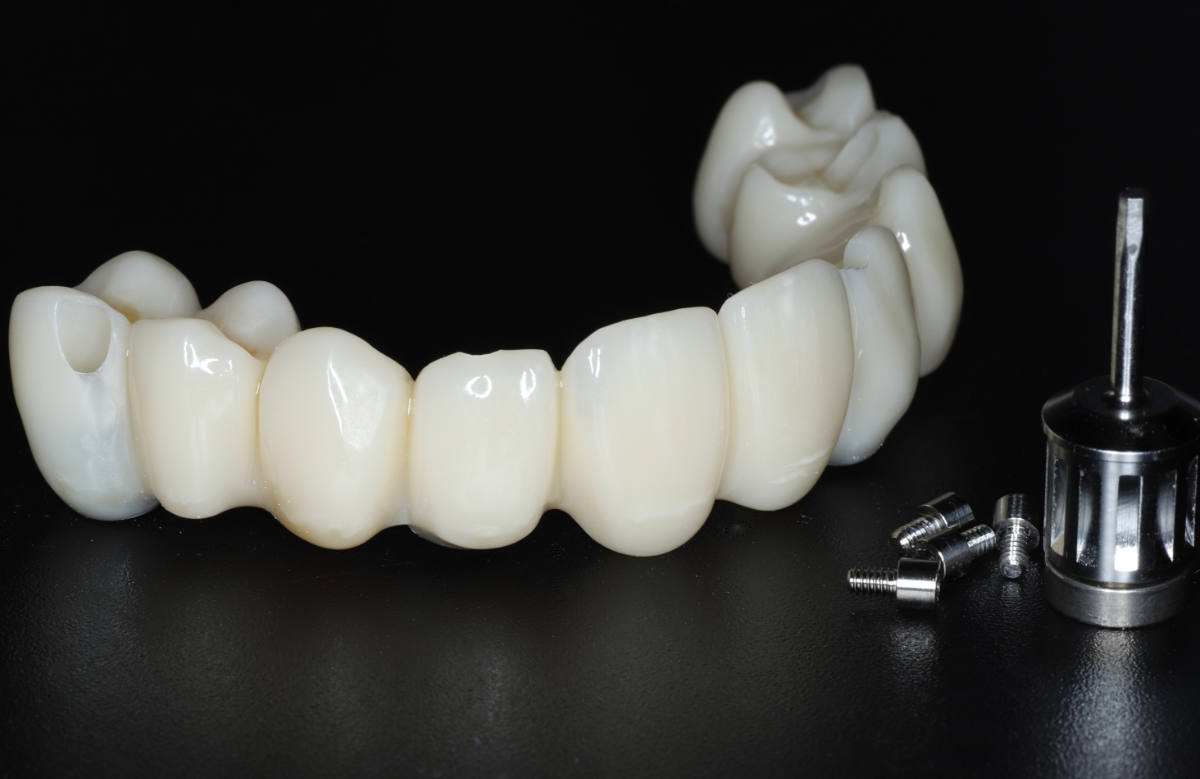

Navigovaná chirurgia, 5 implantátov

Autor práce Dr. Michal Repaši

Zubný technik Vasil Csopej